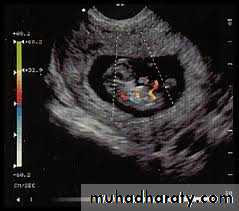

Doppler investigation

Waveforms can be obtained from both the umbilicaland fetal vessels.

Data obtained from the umbilical artery provide indirect information about placenta function, whereas data from the fetal vessels provide information on the fetal response to hypoxia.

Umbilical artery

Waveforms obtained from the umbilical artery provide information on placental resistance to blood flow and hence indirectly placenta ‘health’ and function.An infarcted placenta secondary to maternal hypertension, for example, will have increased resistance to flow

Normal umbilical arterial Doppler waveform

Reverse end diastolic flow in the umbilical arteryusing this technique in clinical practice have looked at resistance to flow, which is reflected in the diastolic component.

A small amount of diastolic flow implies high resistance downstream to the vessel being studied and implies low perfusion .

A high diastolic component indicates low downstream resistance and implies high perfusion.

A measure of the amount of diastolic flow relative to systolic is provided by several indices, such as the pulsatility index or resistance index, which essentially compare the amount of diastolic flow to systolic flow.

When these indices are high, this indicates high resistance to flow; when the indices are low, resistance to flow is low.

Reduced end diastolic flow in umbilical arterycompared to normal

Normally, diastolic flow in the umbilical artery increases (i.e. placental resistance falls) throughout gestation. Absent or reversed end-diastolic flow in the umbilical artery is a particularly serious development with a strong correlation with fetal distress and intrauterine death.